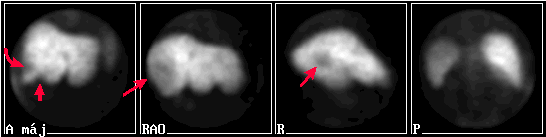

A vizsgálat [Tc-99m] fitáttal készült. A képeken zajcsökkentő (Metz) szűrést végeztünk.

A májban több (elsősorban a nyilakkal jelzett) helyen térfoglaló folyamatra utaló, körülírt aktivitás-csökkenés látható, melyek a májban levő metastasisoknak felelnek meg. (Megjegyzendő, hogy a polycystás máj hasonlóan néz ki.)